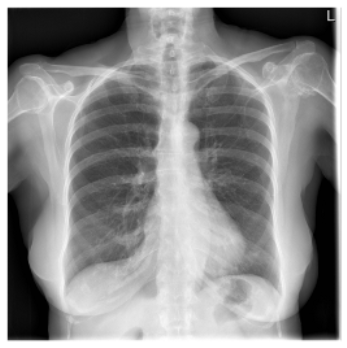

DatasetX-RayGenerated ReportGround Truth

Applsci 16 00470 i002Mild hyperexpansion of the lungs. Numerous bilateral rib deformities. No focal airspace disease. Heart size is normal. No pneumothorax or effusion.The heart size and cardiomediastinal silhouette are normal. There is hyperexpansion of the lungs. There is no focal airspace opacity, pleural effusion, or pneumothorax.